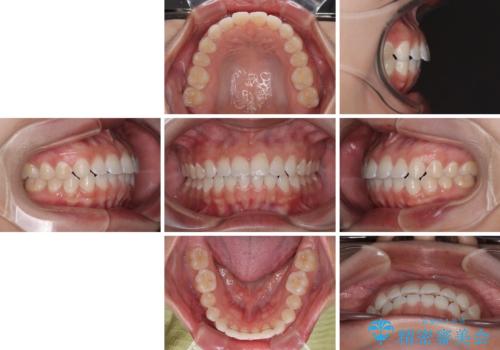

- 上下前歯のデコボコを気にして来院された患者様です。

ワイヤー矯正でもマウスピース矯正でも可能でしたが、短期間で、自身の手を煩わせることなく治療を行いたいとのことで、ワイヤー装置にて矯正治療を行うこととしました。

僅か半年強、あっという間に治療を終えることができました。